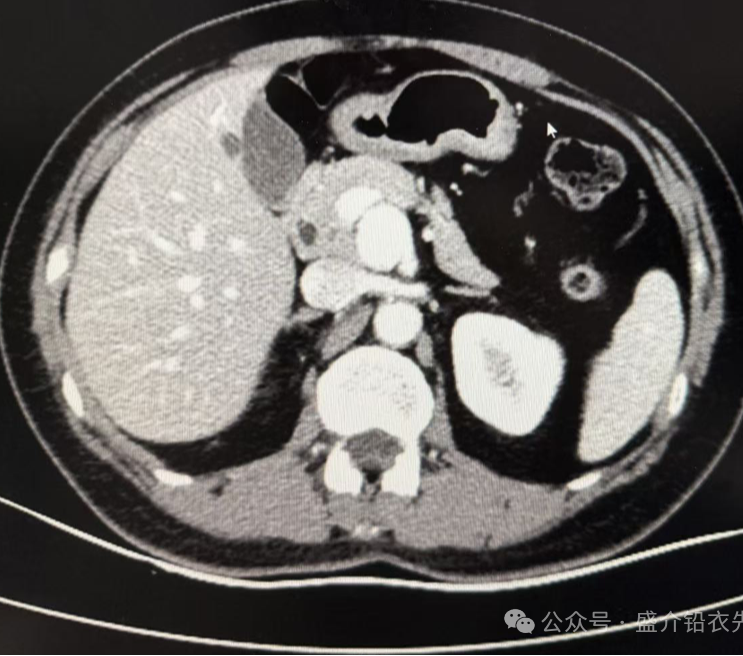

中年女性患者,乳腺癌切除术后复查。发现脾动脉瘤1年。增强CT可见:胰腺颈部后方软组织密度结节,增强动脉期明显强化。大小约:24mm×20mm,与肠系膜上动脉相连接。